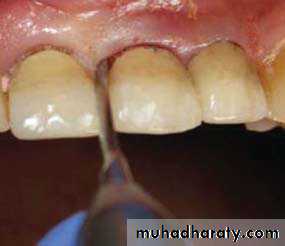

3 -Severe periodontal disease; Bone loss,grade 3 mobility,furaction involvement.